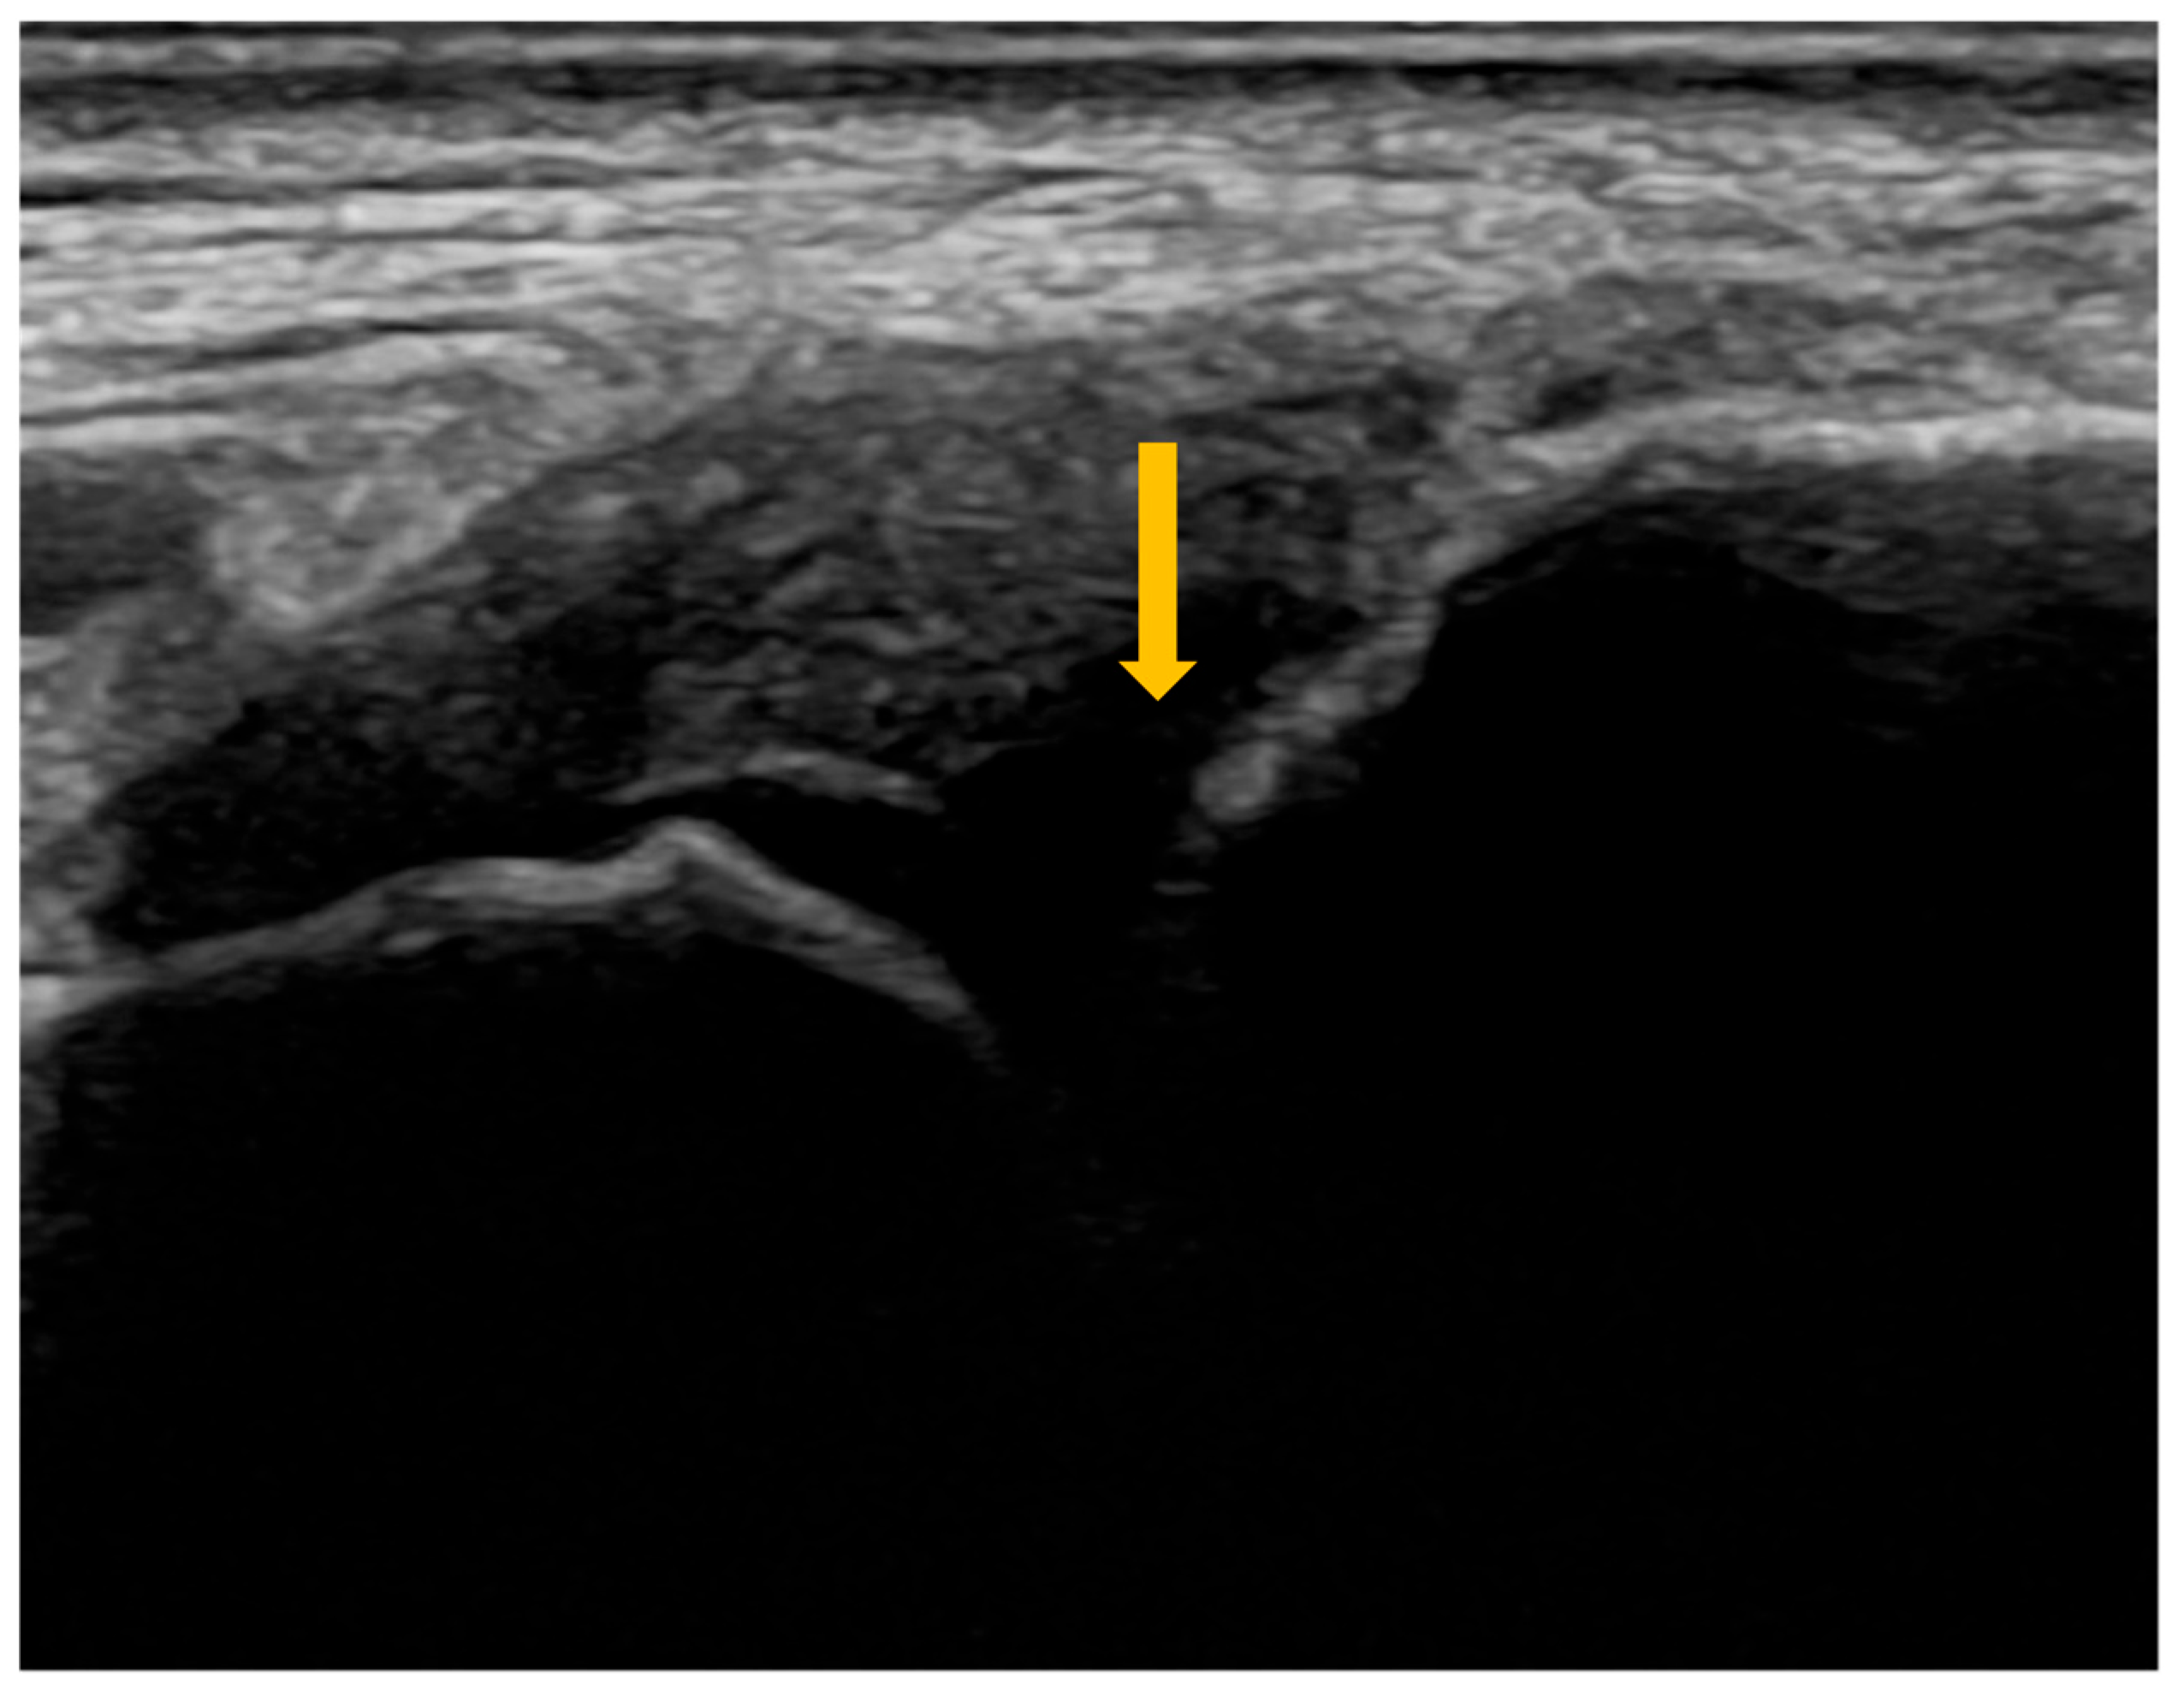

On ultrasound, synovitis is characterized by synovial hypertrophy (Figure 2) and joint effusion, with an increased-color Doppler signal suggestive of vascular congestion [38]. The severity of synovitis is assessed using a semi-quantitative scoring system developed by the OMERACT group (Outcome Measures in Rheumatology), which allows classification of patients into different categories of inflammatory activity (Table 5) [41].

Figure 2. B-mode ultrasound of the right radiocarpal joint demonstrating synovial hypertrophy. Gray-scale (B-mode) ultrasound of the right radiocarpal joint shows synovial hypertrophy, appearing as thickened hypoechoic synovial tissue within the joint recess (arrow), consistent with active inflammation.